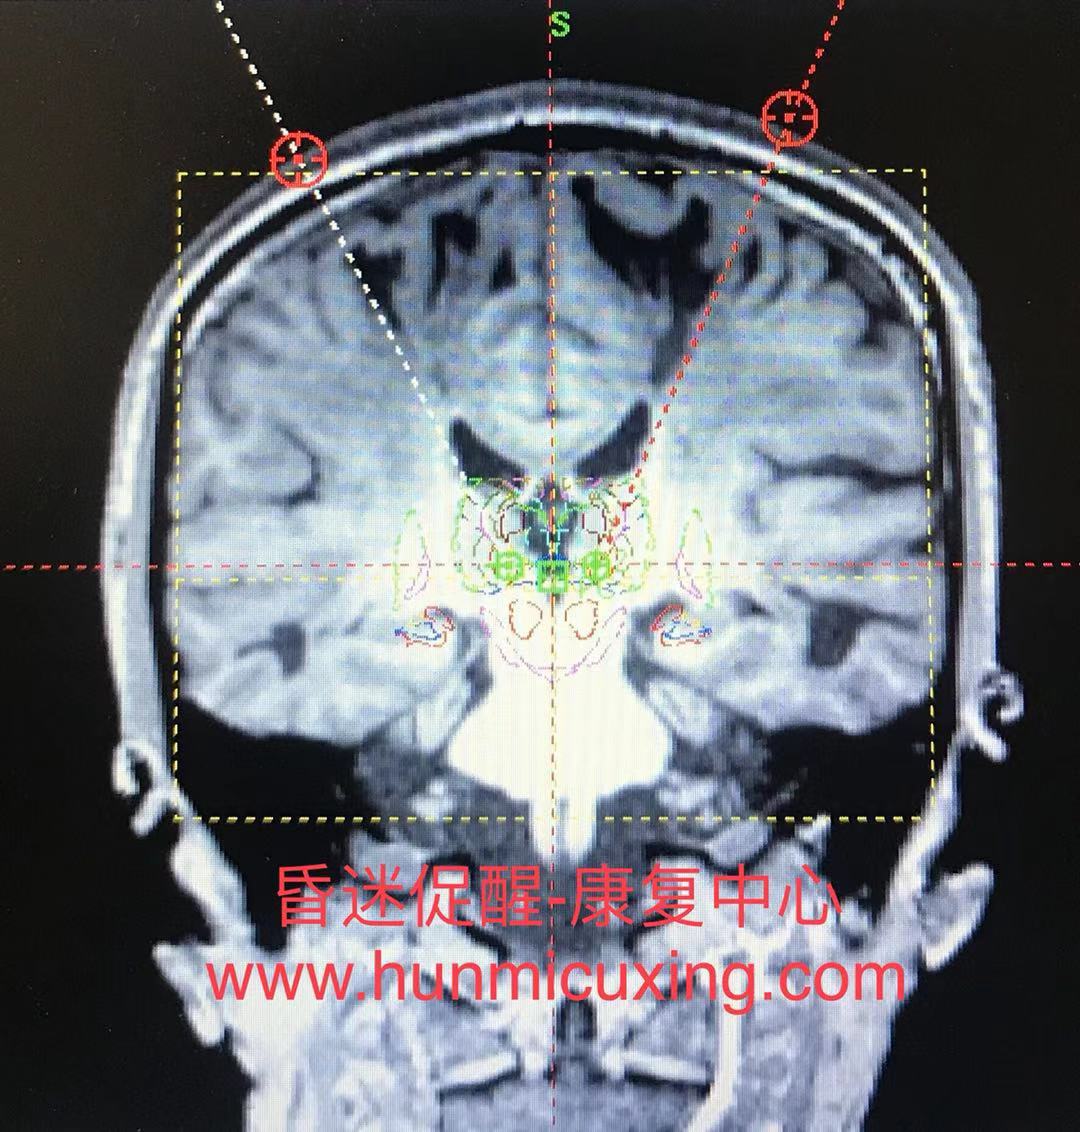

图2:通过向大脑内特定核团进行电刺激促醒患者清醒。

图3:临床上脑干出血如图中白色虚线那样,切断了大脑和身体的联系,使得意识不能够通过语言和行动进行表达,被称为"闭锁综合征"。